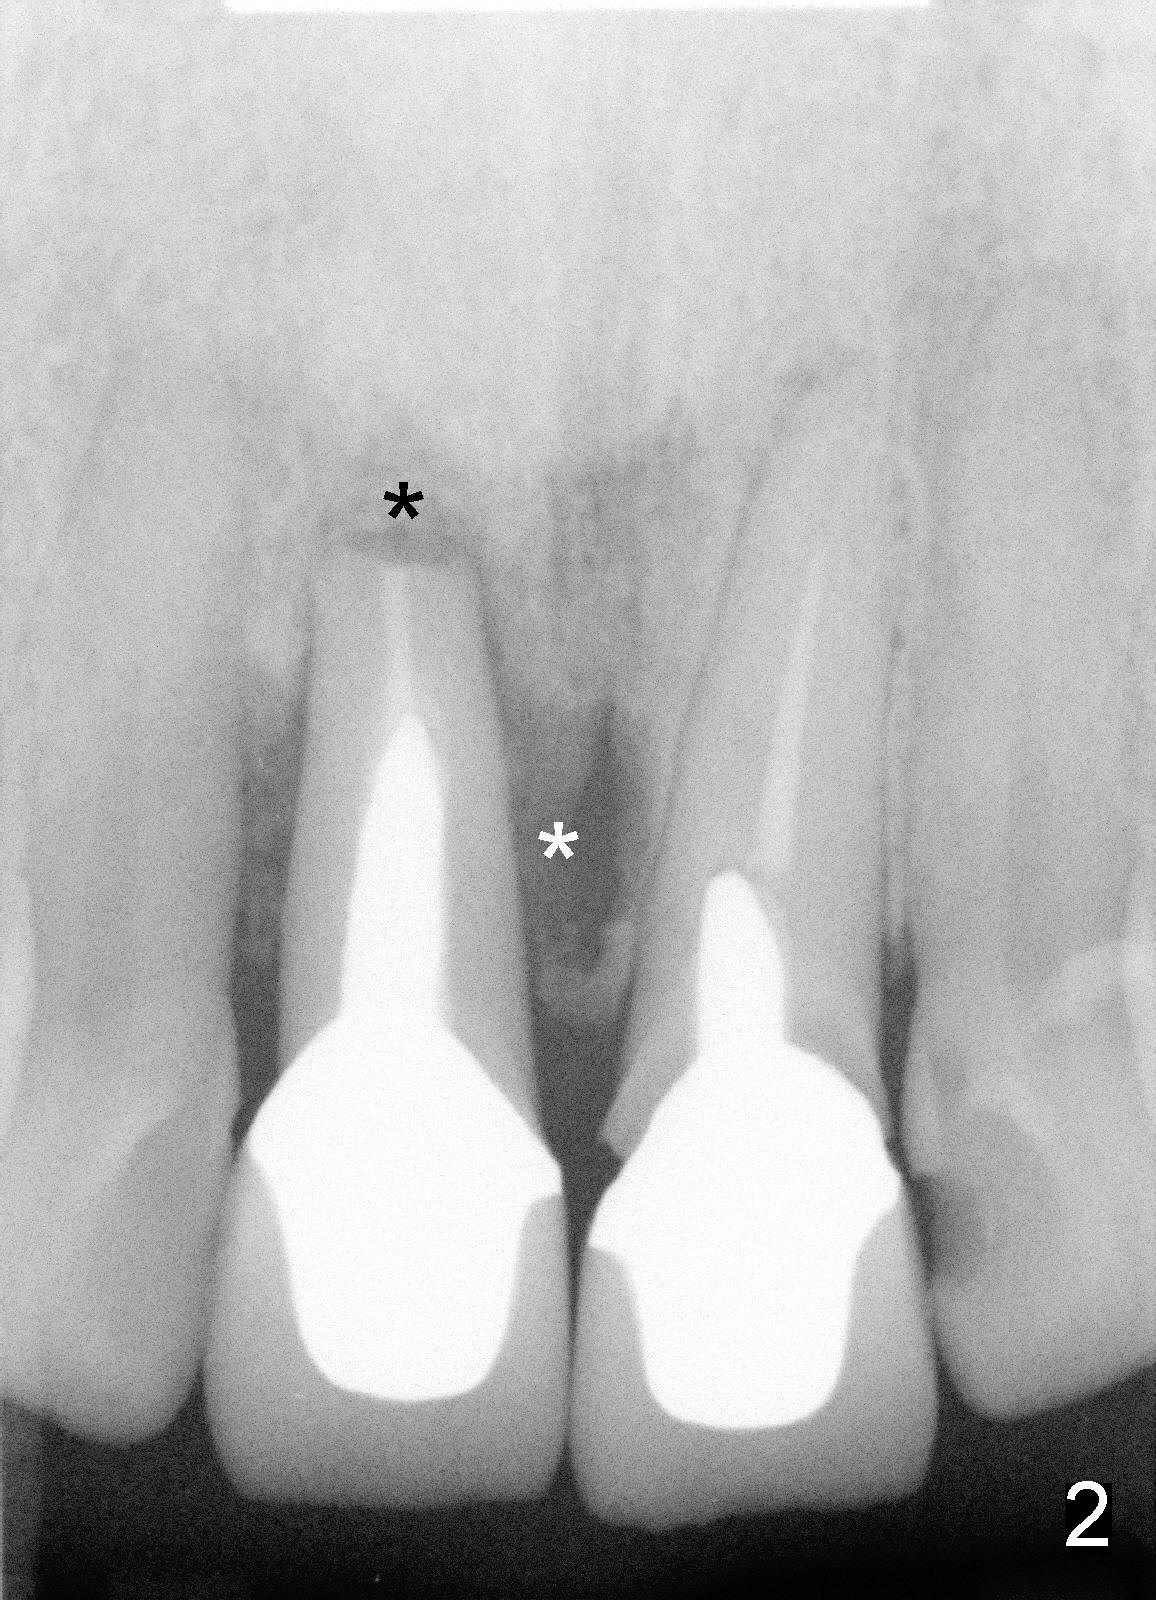

Treatment plan consists of fabrication of temporary crowns (splinting), atraumatic extraction, debridement of sockets (possible labial plate perforation at the site #8), Tetracycline suspension and Chlorhexidine irrigation, osteotomy on palatal wall with drills (Bicon reamers) from 2 mm to 3 or 3.5 mm at slow speed to collect autogenous bone, and placement of 5x20 Tatum tapered implants (Fig.3). Raise flap to expose labial plate perforation, place autogenous bone graft in the defect and around the implants and place collagen membrane for guided bone regeneration. If initial stability of implants is achieved, place 4 mm abutments immediately, reline splinted temporary crowns, and cementation.